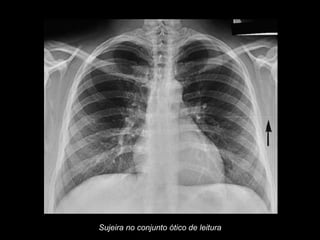

Sujeira no conjunto ótico de leitura

Sujeira no conjuntoótico de leitura